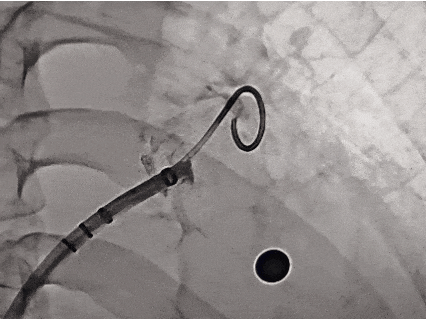

封堵器释放后评估

符合PASS释放原则,释放封堵器

释放后造影,无残余分流

释放后封堵器形态良好,封堵完全

术中采用退鞘法进行封堵器展开,封堵器展开后肝位即刻造影,封堵器肩部位于左心耳开口处,位置合适,上下缘无造影剂漏;牵拉时有明显回弹,且牵拉后封堵器位置无移动;测量其压缩比为14.4%,符合PASS释放原则,释放后封堵器形态良好,位置稳定,造影无残余分流,无露肩。